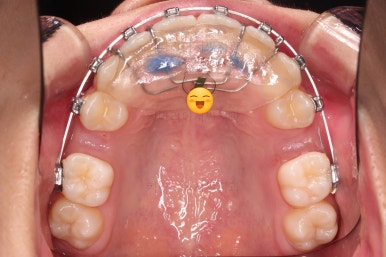

윗니가 가지런해진 뒤에는 부산치아교정치과 키다리아저씨치과에서는 ABP라고 하는 장치를 사용해 주면서 아랫니에도 브라켓을 부착합니다.

깊게 물리는 과개교합을 개선하기 위함인데요.

과개교합을 개선하기 위해서는 미니스크류를 사용하기도 하고 ABP를 사용하기도 하며, 윗니 앞니를 코 방향으로 밀어넣기도 합니다.

얼굴모습과 교합을 생각해서 각 케이스마다 모두 다른 방법을 적용해야 하므로 일관된 공식이 있는 것이 아닙니다.

이번 환자분은 ABP의 사용이 가장 적합했던 케이스였습니다.

ABP를 사용하지 않고도 과개교합이 매우 좋아졌고요.

부산치아교정치과 키다리아저씨치과에서 마무리한 입안의 모습입니다.

가지런하게 잘 정렬이 되었고요.

윗니만 발치한 편악발치교정이지만 틈새 없이 공간이 닫혔으며 교합도 잘 맞습니다.